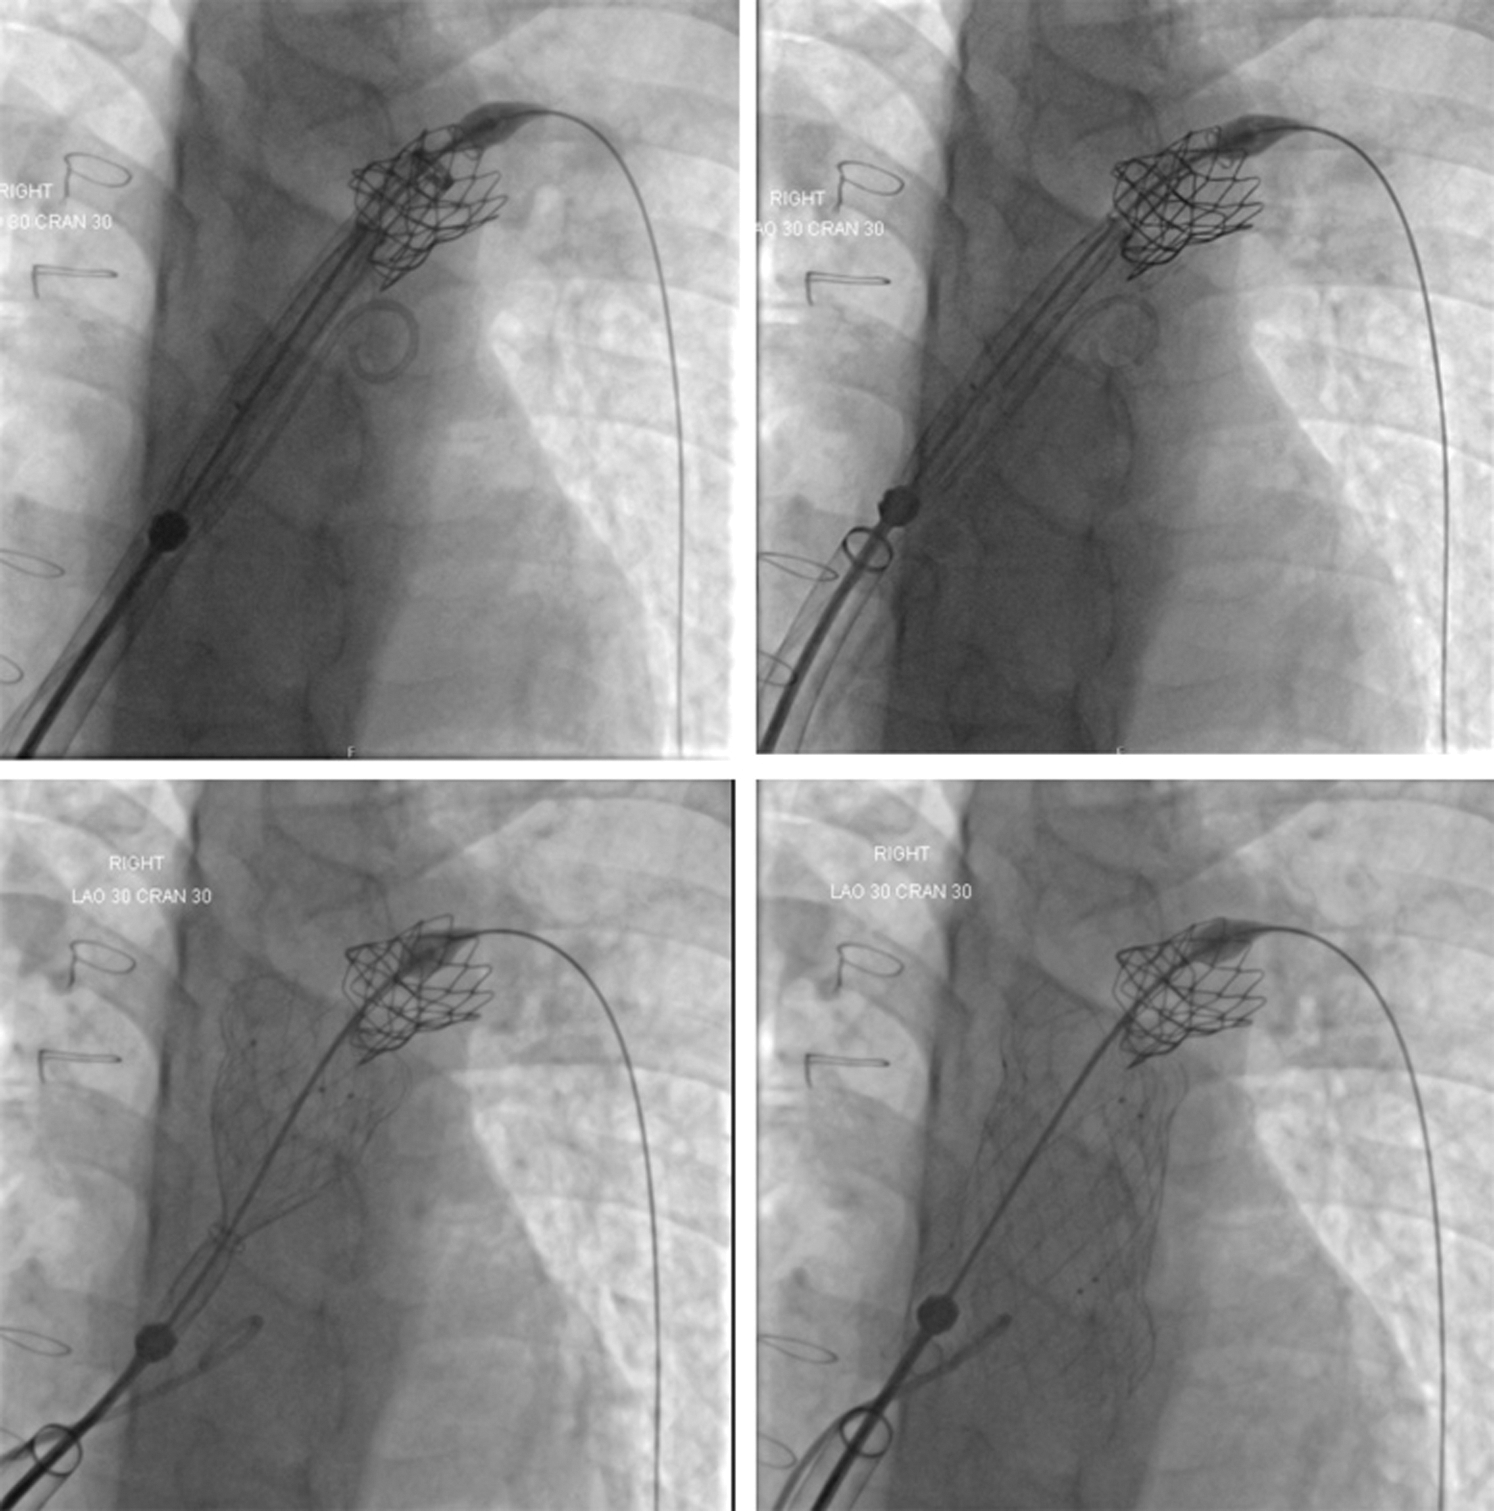

Surgical right ventricular outflow tract (RVOT) enlargement for congenital heart diseases such as tetralogy of Fallot (ToF), particularly including a transannular patch to abolish obstruction, results in pulmonary regurgitation. Severe pulmonary regurgitation may cause progressive dilatation and dysfunction of the right ventricle, a decrease in exercise tolerance, arrhythmias, and eventually right heart failure and increased risk of sudden death [1]. Historically, most children and young adults in whom there was an indication for implantation of a competent pulmonary valve were referred for surgery. However, many centres now consider a percutaneous approach to their management to be the first-line therapy. Use of the commercially available transcatheter valves-the Melody valve (Medtronic, Minneapolis, MN, USA) and the SAPIEN series of valves (Edwards Lifesciences, Irvine, CA, USA) - is limited by their maximum dimensions and the fact that a significant proportion of patients, who have undergone ToF repair using a transannular patch, have RVOT dimensions larger than those suitable for either of these valves. The Venus P-valve (Venus MedTech, Hangzhou, China) is a self-expanding percutaneous valve that has been used in several studies in humans in series from Asia (3), Europe (4) and South America (5) with good medium-term results both in Chinese (6) and international (7) studies. Transcatheter implantation of pulmonary valves can be difficult due to various reasons including rigidity of the valve delivery system, as for Venus P-Valve, softness of delivery system, as with the Melody or SAPIEN valves, or the anatomy of the RVOT and pulmonary artery bifurcation. Furthermore, in particular in patients in whom a SAPIEN valve is implanted, the fact that the valve is manoeuvred without being covered may result in tricuspid valve injury [9]. Experienced operators have reported modifications of techniques to overcome these difficulties [10]. The use of a long sheath rigid enough to provide safe delivery may ease the procedure and reduce the risks [11]. Use of the GORE® DrySeal sheath has been proven useful in the implantation of SAPIEN valves in a recently published multicentre study [8]. The implantation of Venus P valve has also its own difficulties due to stiffness of commercially available long-sheath. Therefore, we decided to modify the previously described techniques of implanting the Venus P-valve in the pulmonary position after surgical repair of congenital heart disease [3–7]. To date, all attempts to deploy the Venus P-valve using this technique have been successful. Furthermore, lower procedural and fluoroscopy times were found when compared with the group where the GORE® DrySeal was not used. These differences may be related to multiple factors, and not only to GORE® DrySeal use, including institutional learning curve. Furthermore, previous studies have described failure to deploy a Venus P-valve in a patient with a previously placed LPA stent due to difficulty in advancing the delivery sheath into the LPA, causing a break in the delivery sheath. Subsequently, the presence of an LPA stent has been considered a relative contraindication to Venus P-valve implantation [7]. In our patient with an in situ LPA stent, it was straightforward to advance the GORE® DrySeal sheath over a Lunderquist wire and through the LPA stent after pre-dilatation of the stent with a high-pressure balloon allowing uneventful implantation of a Venus-P-valve without complications (Fig. 3). Finally, even it is usually considered that the placement of the guidewire in the left pulmonary artery is advised and/or preferred, it is also possible to consider placing the guidewire in the right pulmonary artery in selected cases when a better orientation of the delivery system is anticipated.

Figure 3: Fluoroscopic AP with cranial angulation views